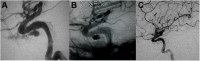

Intracranial pseudoaneurysms account for about 1% of intracranial aneurysms with a high mortality. The natural history of intracranial pseudoaneurysm is not well-understood, and its management remains controversial. This review provides an overview of the etiology, pathophysiology, clinical presentation, imaging, and management of intracranial pseudoaneurysms. Especially, this article emphasizes the factors that should be considered for the most appropriate management strategy based on the risks and benefits of each treatment option.